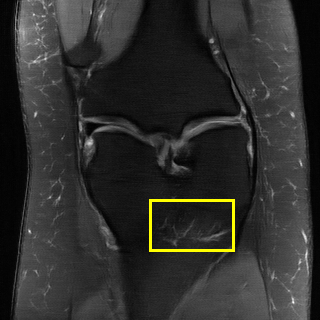

EPN is utilized to provide edge priors for later reconstruction, so the quality of the predicted edges is very important. In Fig. 10, we provide some qualitative results of the predicted edges of EPN on three multi-coil datasets. Among them, the GT edges are extracted using the Sobel operator. As can be seen from the images, our proposed EPN can predict an approximate contour for the overall subject and can reconstruct accurate edges close to the GT edges under two acceleration factors. This fully verifies the effectiveness and excellence of the proposed EPN.

Edge preserving has always been a crucial concern in the design of reconstruction models. To improve the quality of reconstructed images and preserve image edges, some works suggested introducing edge priors in the original restoration problem to preserve image edges [4, 34]. However, they will suffer from complicated algorithm design and time-consuming training processes. Recently, some more efficient methods have been proposed to use edge maps as external guidance for image restoration. For example, Yang et al. [48] used off-the-shelf edge detectors to extract image edges from the degraded images. Fang et al. [12] predicted image edges by constructing an edge reconstruction network. Huang et al. [18] designed a novel dual discriminator GAN framework for solving fast multi-channel MRI, in which one GAN network is built for edge information enhancement. Inspired by these methods, we also consider introducing image edge prior as external guidance to MRI reconstruction since 1) image edges are prominent and distinguishable features in MRI (see Fig. 1), which can serve as a good guide to the model to recover high-frequency details; 2) the ground truth edges can be easily fetched via ordinary edge extraction operators, like Canny, Sobel, and Prewitt, which means that the edge maps can be learned in a data-driven manner. However, how to effectively utilize image edge priors to guide image reconstruction still remains a challenge. In some methods, edge information was simply concatenated with the input image and passed to the next stages. Though this is a simple way to utilize the edge priors, it may not give full play to the guiding role of the edge priors. Therefore, in this work, we want to explore a more efficient and effective mechanism to fully take advantage of image edge priors.

fastMRI is a large-scale MR dataset jointly established by Facebook AI Research and NYU Langone Health. It provides both knee and brain datasets for evaluation. In our work, we use the multi-coil knee dataset, which was acquired on three clinical 3T systems or one clinical 1.5T system using a 15-channel knee coil array. The dataset includes data from two pulse sequences, yielding coronal proton-density weighting with (PDFS) and without (PD) fat suppression. As is shown in Fig. 1, PD images usually contain more structural and prominent edge features than PDFS images, which suggests that it is more challenging to use edge guidance on PDFS datasets. Therefore, we explore the effectiveness of EAMRI on these two modalities. Following [13], for both PD and PDFS knee datasets, we separately filter out 227 volumes (8332 slices) for training and 24 volumes (1665 slices) for testing. The dataset is centrally cropped to .